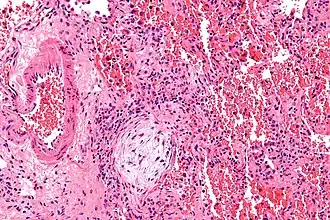

Micrographie montrant un corps de Masson (excentré à gauche/en bas de l'image - circulaire pâle et paucicellulaire), tel qu'on peut l'observer dans la pneumonie organisatrice cryptogénique. Le corps de Masson obstrue les voies respiratoires. L'artère associée à la voie respiratoire oblitérée est également visible (à l'extrême gauche de l'image). Coloration à l'hématoxyline et à l'éosine.